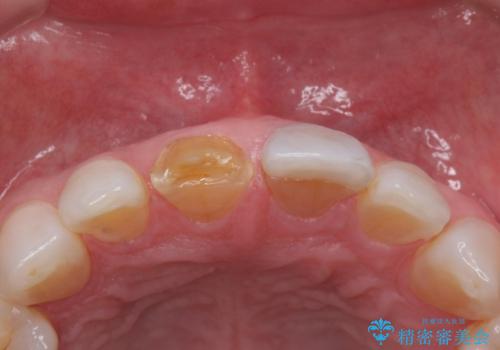

- 前歯につけていたべニアが取れたとのことで来院された患者様です。

より脱離リスクの低いクラウンでの修復を行います。

- 右上1左上1 : 仮歯/11,000円×2、ジルコニアクラウン(スペシャル)/154,000円×2 合計330,000円(税込)費用は治療当時の料金となります